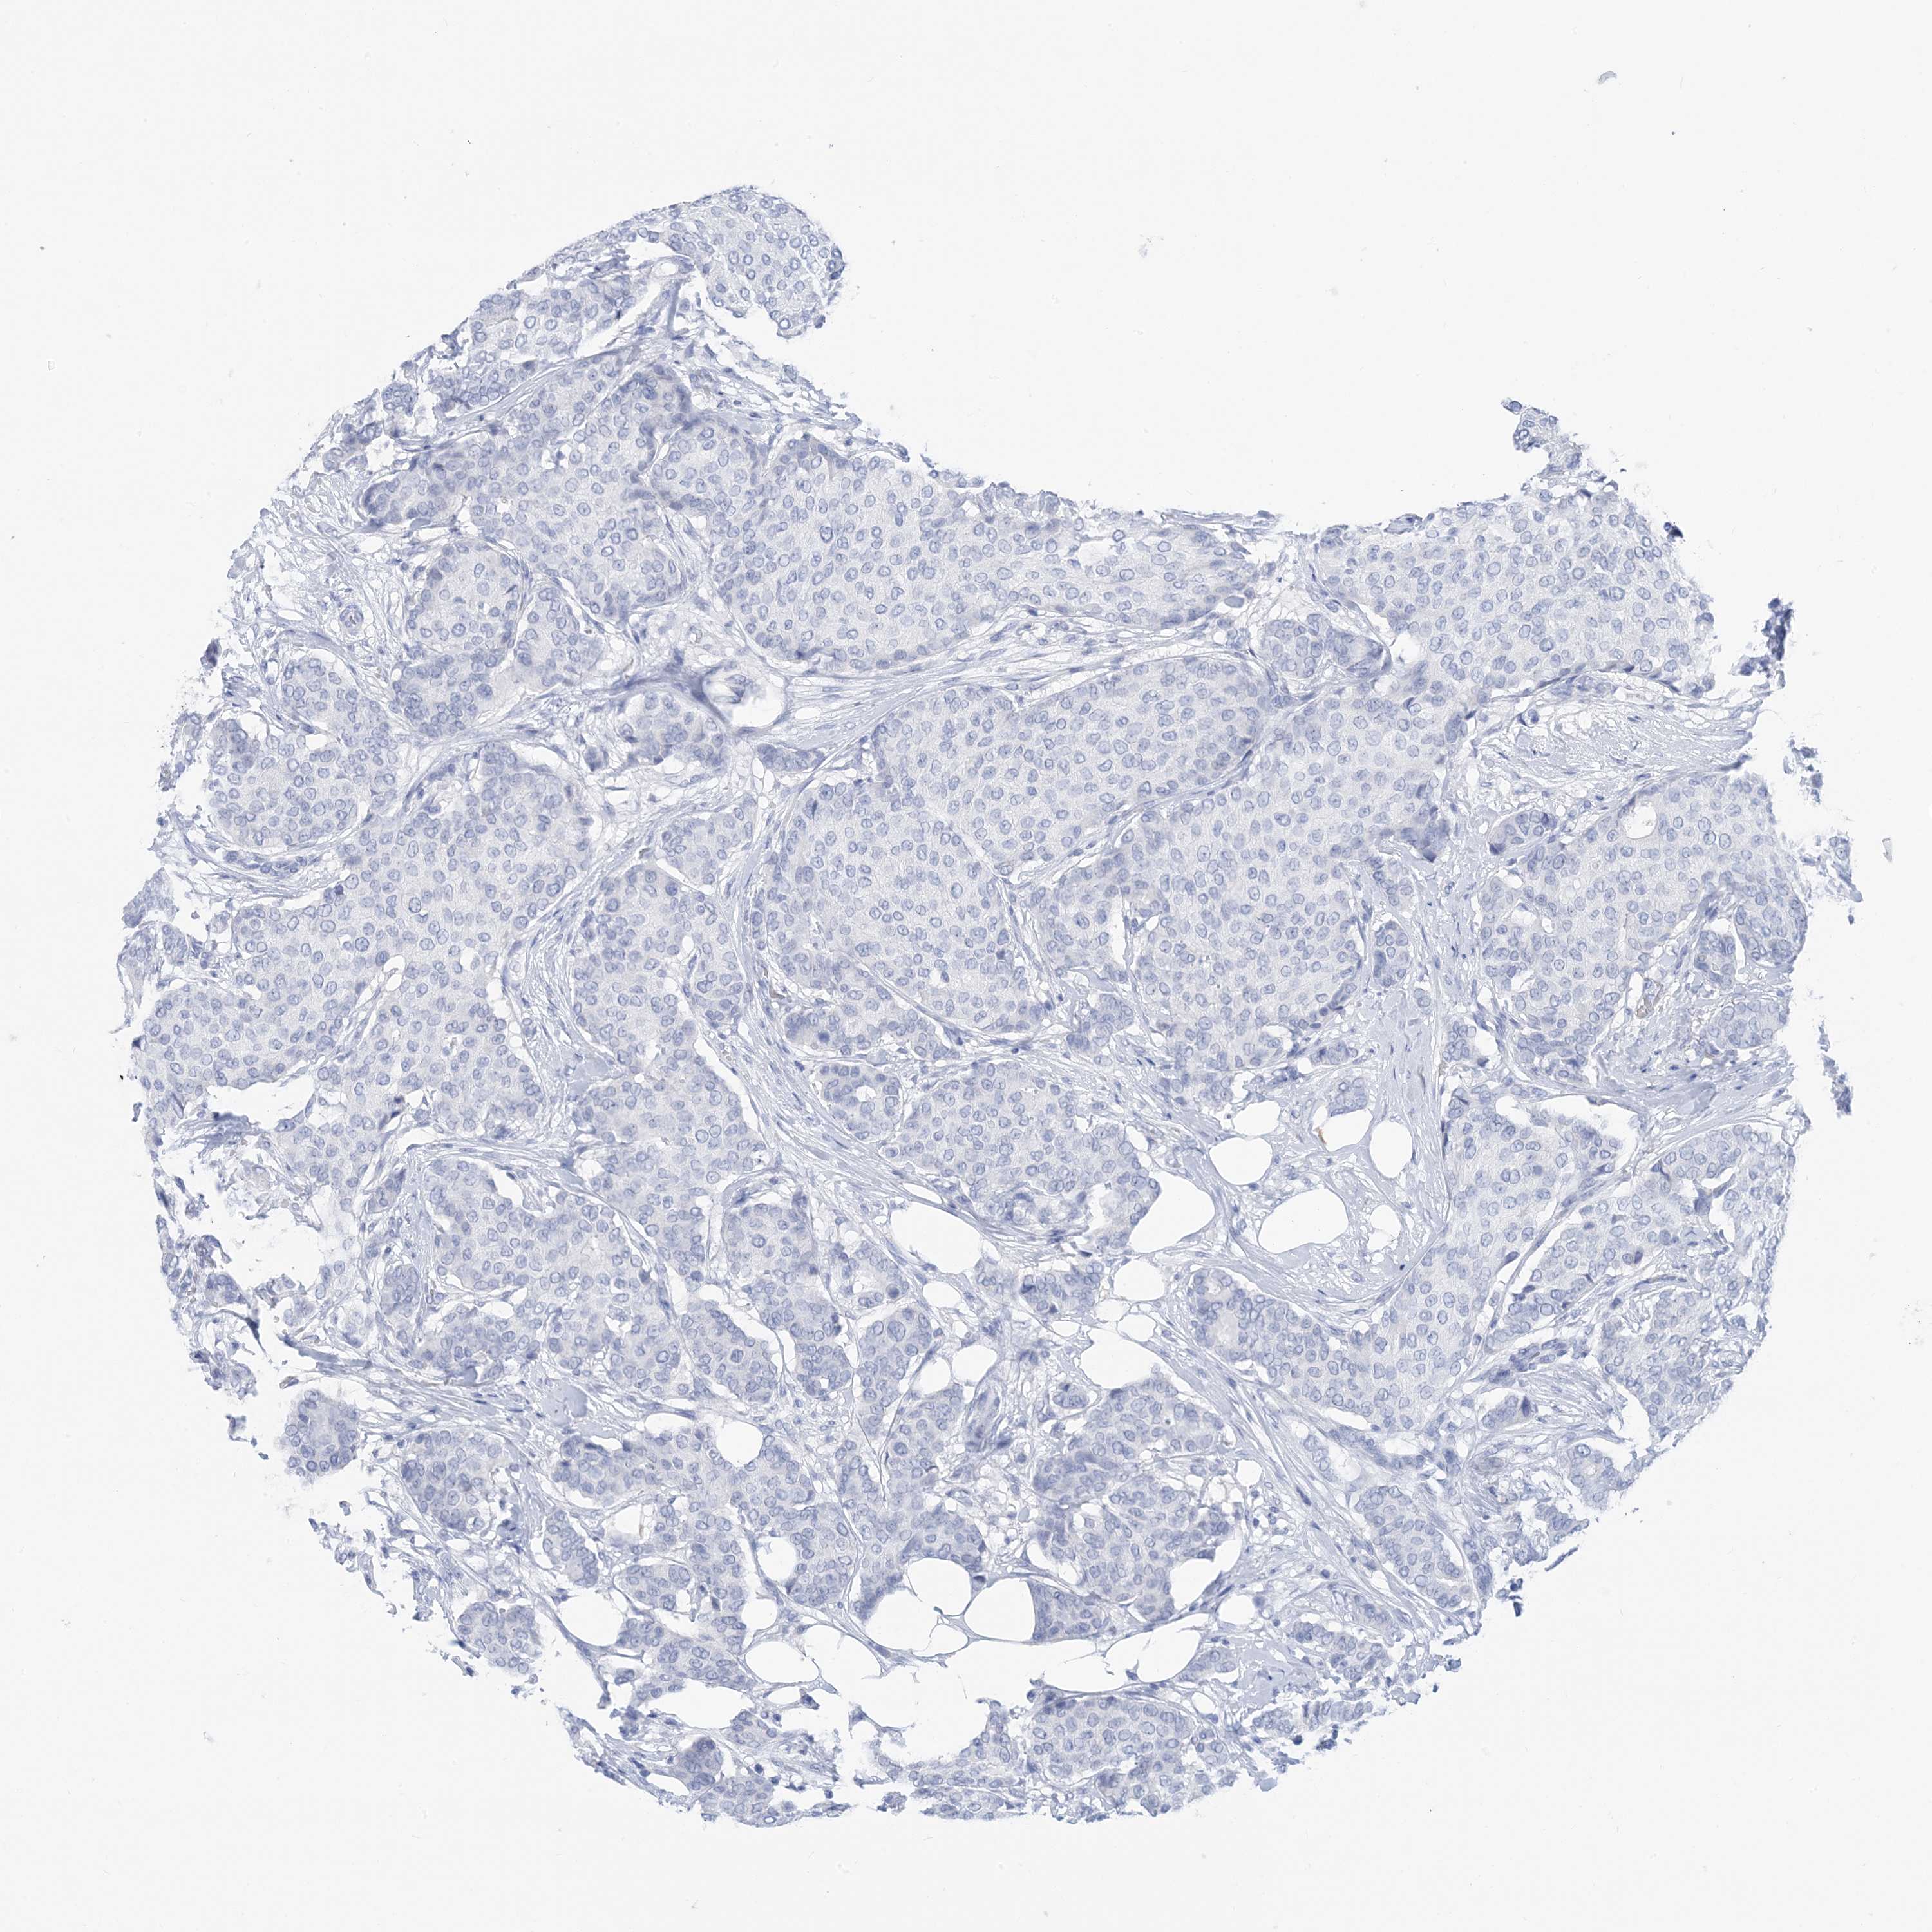

CANCER BREAST CANCER Show tissue menu

Breast cancer

Human cancer